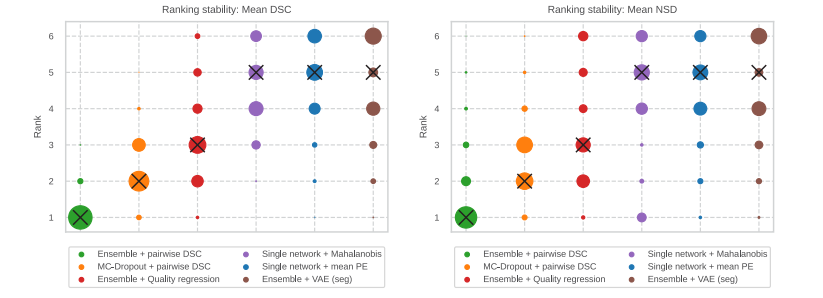

Fig. 5. Impact of the choice of segmentation metric as a risk function on the ranking stability, comparing mean DSC (left) and NSD (right). Bootstrapping (𝑁 = 500) was used toobtain a distribution of ranks for the results of each fold and the ranking distributions of all folds were accumulated. All ranks across datasets are combined in this figure, wherethe circle area is proportional to the rank count and the black x-markers indicate median ranks, which were also used to sort the methods. Overall, the ranking distributionsare similar for mean DSC and NSD. The variance in the ranking distributions largely originates from combining the rankings across datasets, so for each dataset individually theranking is more stable (see for example the Covid dataset in fig. B.12)

图5. 分割度量选择作为风险函数对排名稳定性的影响,比较平均DSC(左图)和NSD(右图)。使用自助法(𝑁 = 500)来获取每个折次结果的排名分布,并累积所有折次的排名分布。在此图中,所有数据集的排名合并在一起,圆形的面积与排名数量成正比,黑色×标记表示中位数排名,这些排名也用于对方法进行排序。总体而言,平均DSC和NSD的排名分布相似。排名分布的方差主要来自于跨数据集合并排名,因此对于每个单独的数据集,排名会更稳定(例如,见图B.12中的Covid数据集)。